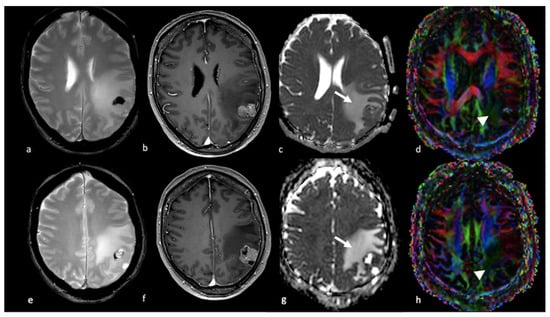

3.2.2. Diffusion Tensor Imaging (DTI)

- Byrnes, T.J.; Barrick, T.R.; Bell, B.A.; Clark, C.A. Diffusion tensor imaging discriminates between glioblastoma and cerebral metastases in vivo. NMR Biomed. 2011, 24, 54–60. [Google Scholar] [CrossRef] [PubMed]

- Sternberg, E.J.; Lipton, M.L.; Burns, J. Utility of diffusion tensor imaging in evaluation of the peritumoral region in patients with primary and metastatic brain tumors. AJNR Am. J. Neuroradiol. 2014, 35, 439–444. [Google Scholar] [CrossRef]

- Tan, Y.; Wang, X.C.; Zhang, H.; Wang, J.; Qin, J.B.; Wu, X.F.; Zhang, L.; Wang, L. Differentiation of high-grade-astrocytomas from solitary-brain-metastases: Comparing diffusion kurtosis imaging and diffusion tensor imaging. Eur. J. Radiol. 2015, 84, 2618–2624. [Google Scholar] [CrossRef]

- Wang, S.; Kim, S.; Chawla, S.; Wolf, R.L.; Knipp, D.E.; Vossough, A.; O’Rourke, D.M.; Judy, K.D.; Poptani, H.; Melhem, E.R. Differentiation between Glioblastomas, Solitary Brain Metastases, and Primary Cerebral Lymphomas Using Diffusion Tensor and Dynamic Susceptibility Contrast-Enhanced MR Imaging. Am. J. Neuroradiol. 2011, 32, 507–514. [Google Scholar] [CrossRef] [PubMed]